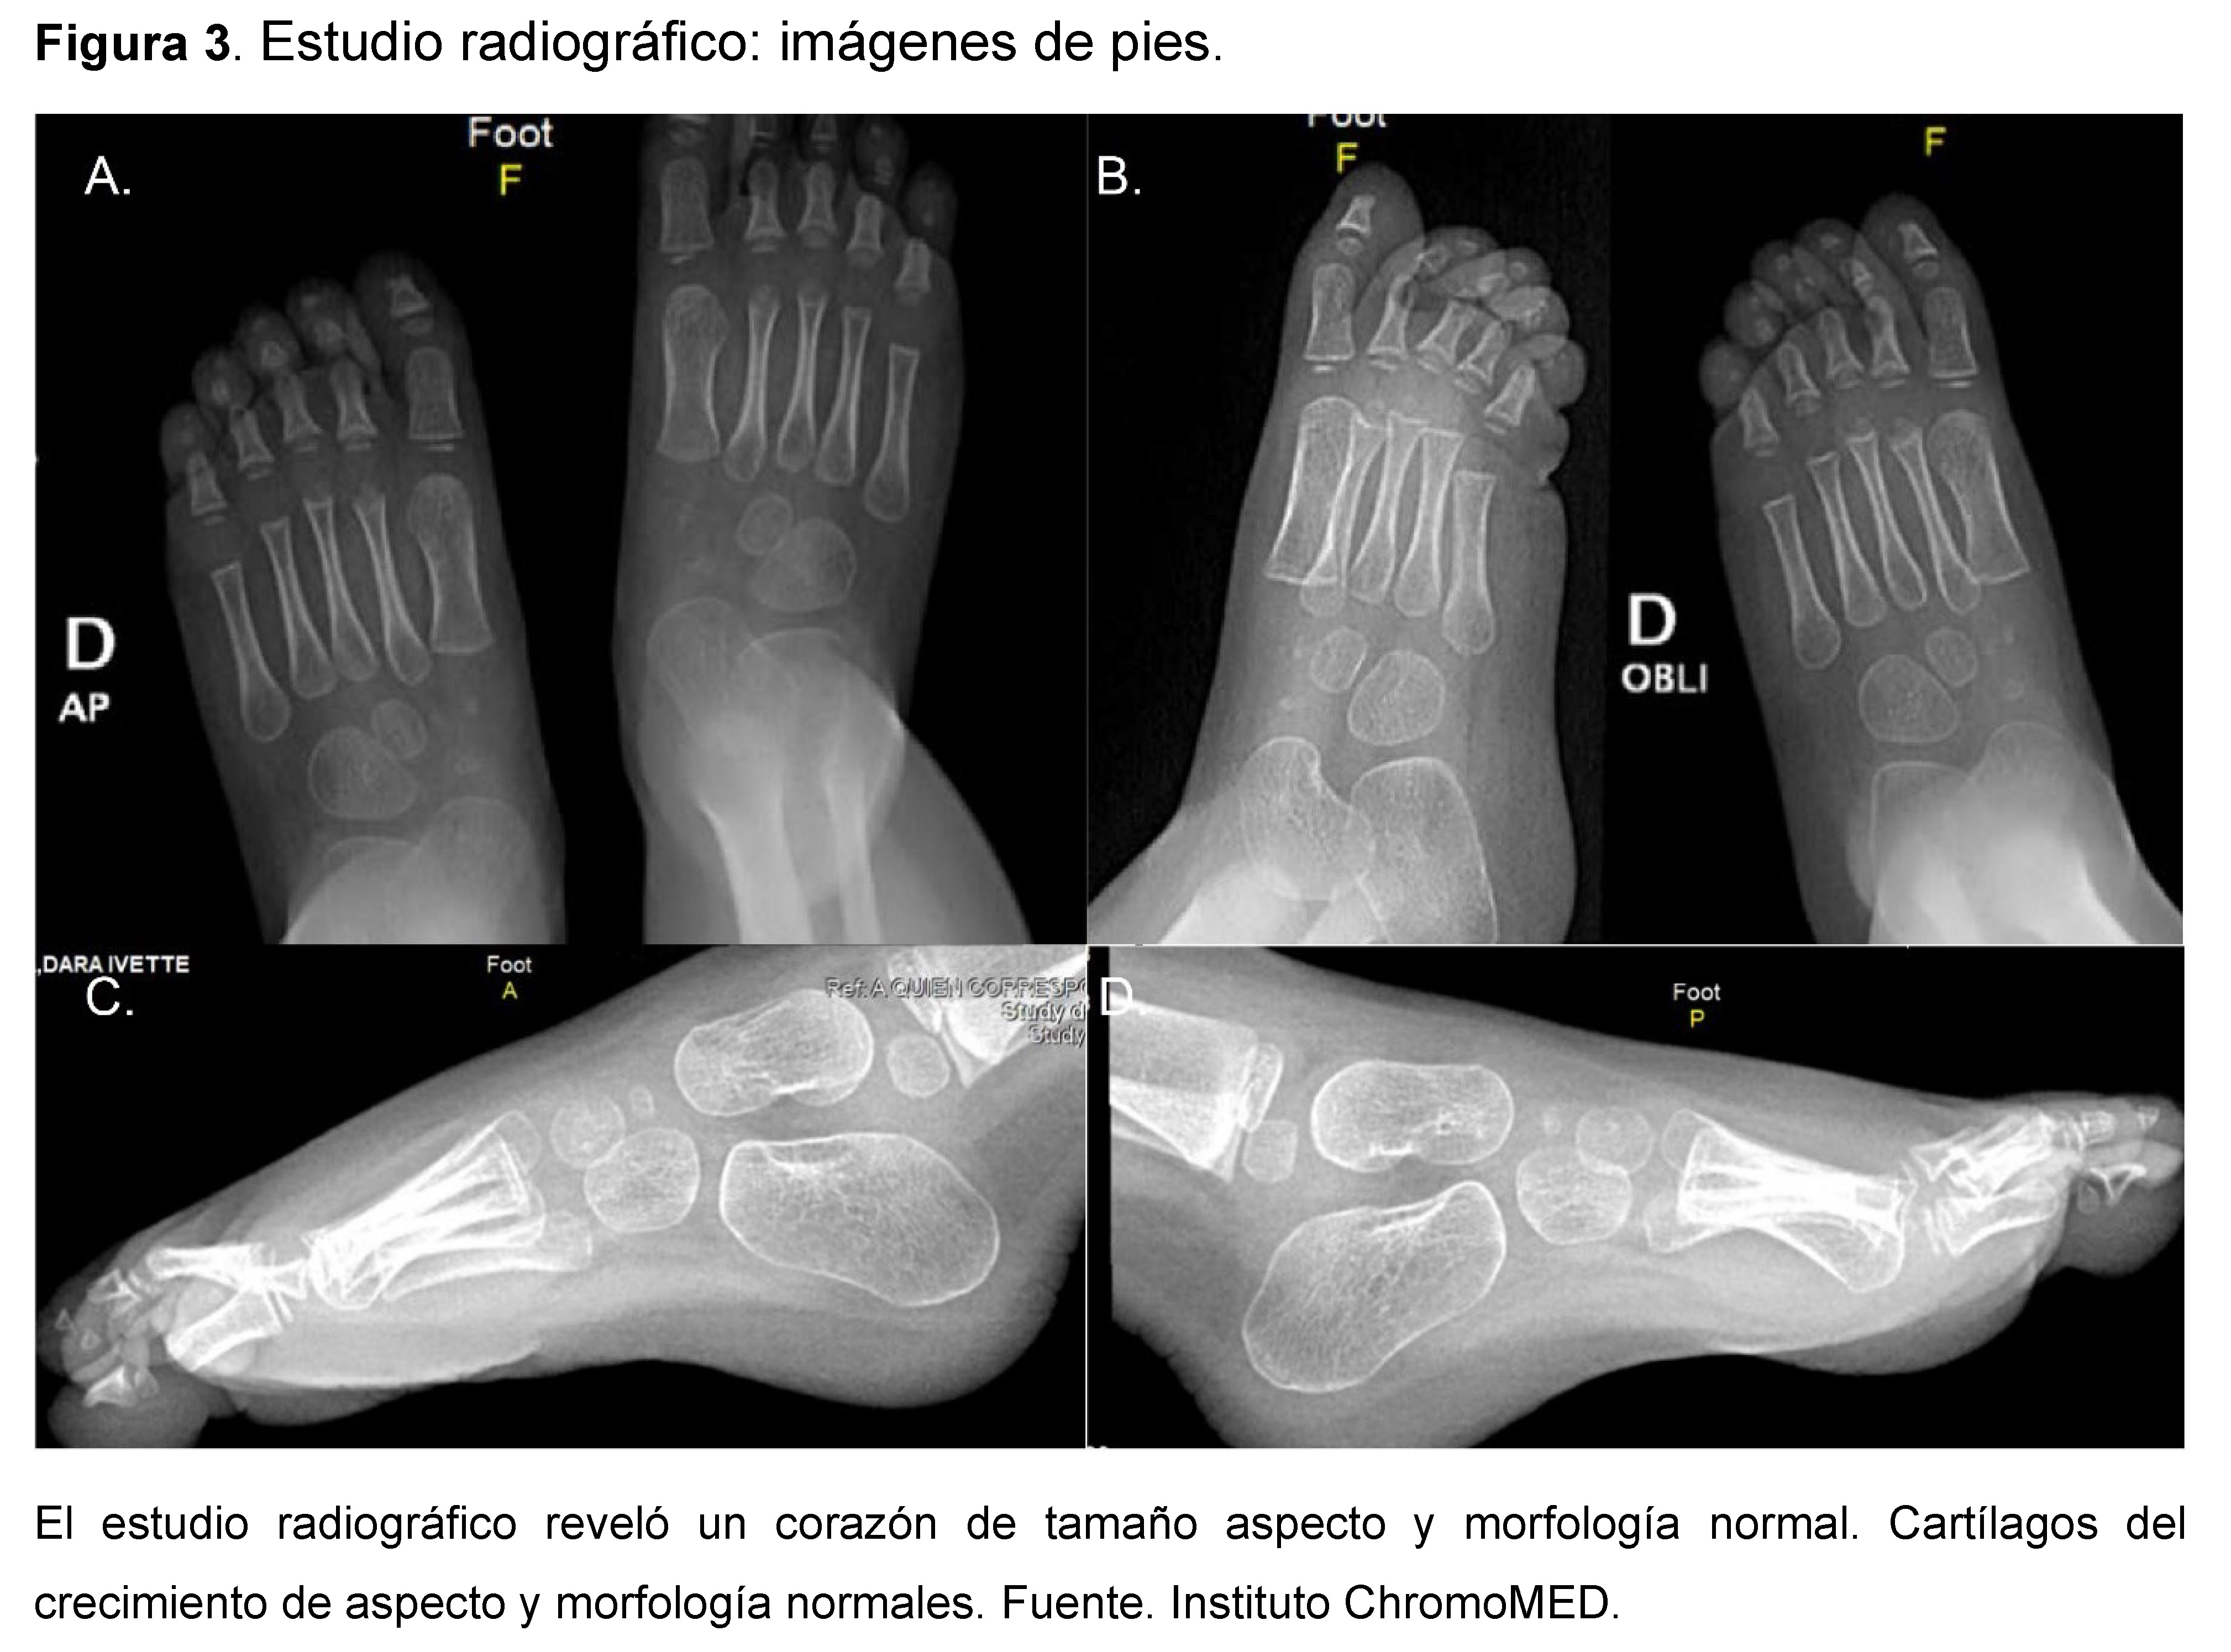

El estudio radiográfico reveló un corazón de tamaño aspecto y morfología normal, con índice cardiotorácico de 0.46 mm (Ver figura 2). Pelvis Platipeloide con morfología ósea dentro de los parámetros de normalidad, cartílagos del crecimiento de aspecto y morfología normales (Ver figura 3).